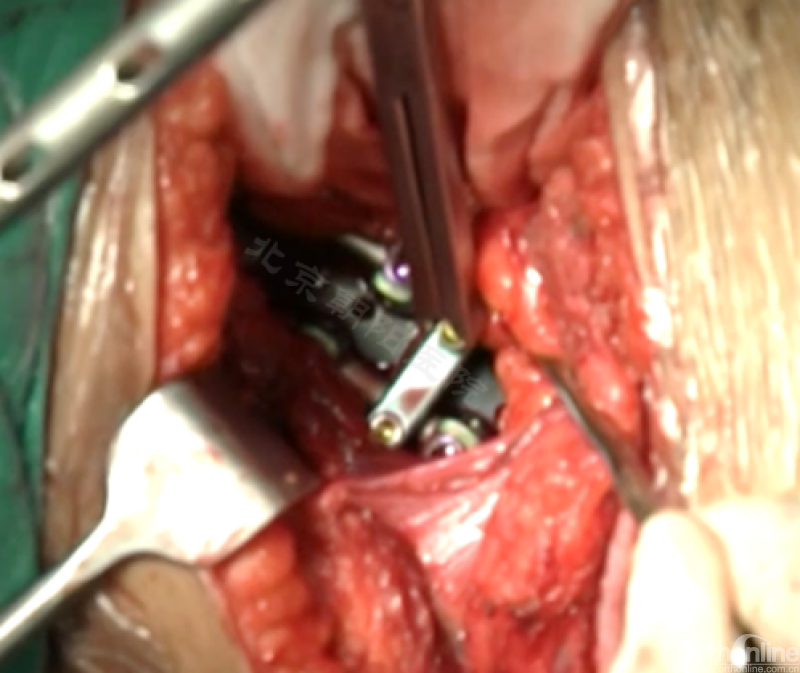

内固定选择的是5.5mm双棒系统,先置入顶椎的螺钉垫板。

置入顶椎的椎体螺钉,螺钉可置入椎体中部到后方1/3之间的范围内。

使用双棒系统时,先置入背侧的螺钉,螺钉指向椎体中线,后置入腹侧的螺钉,螺钉轻度指向后侧。形成对椎体的三角形抓持力。

胸腔侧、腹腔侧螺钉全部置入后,骨移植物植人的越靠近后纵韧带或者纤维环的后缘越好。

将预先折弯的金属棒先置入背侧。

置入腹侧金属棒。

使用双棒系统时先安装背侧的棒,可进行90°的去旋转,也可以直接通过前方螺钉矫正冠状面和矢状面的畸形,然后固定后方的棒,可进一步通过加压矫正冠状面畸形。

矫正后神经检测未见异常术中唤醒患者下肢活动良好,术中透视矫正效果满意、内固定位置良好。根据手术具体情况放置合适尺寸的横连接加强内固定。